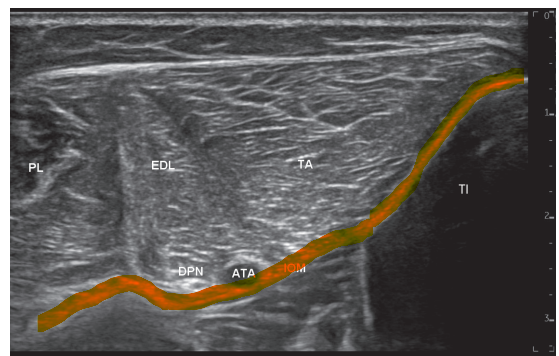

제가 집필한 '초음파로 보는 알짜근육학'에 수록된

족삼리혈의 표준 영상인데요.

여기서 빨간색으로 표시한

골막과 근막층이 치료 타겟이 됩니다.

혈 자리 주변 동맥과 신경의 위치를

초음파로 보면서

골막까지 자극해주고요.

깊은 근막층에도

염증 완화에 효과적인

PDRN 연아약침을 시술합니다.

이번 연구에서 심비골신경(DPN)을 절제한 경우

치료 효과가 재현되지 않았기 때문에

깊은 근막을 타고 혈관과 신경 주변까지

약물이 접촉되도록 시술해야 합니다.